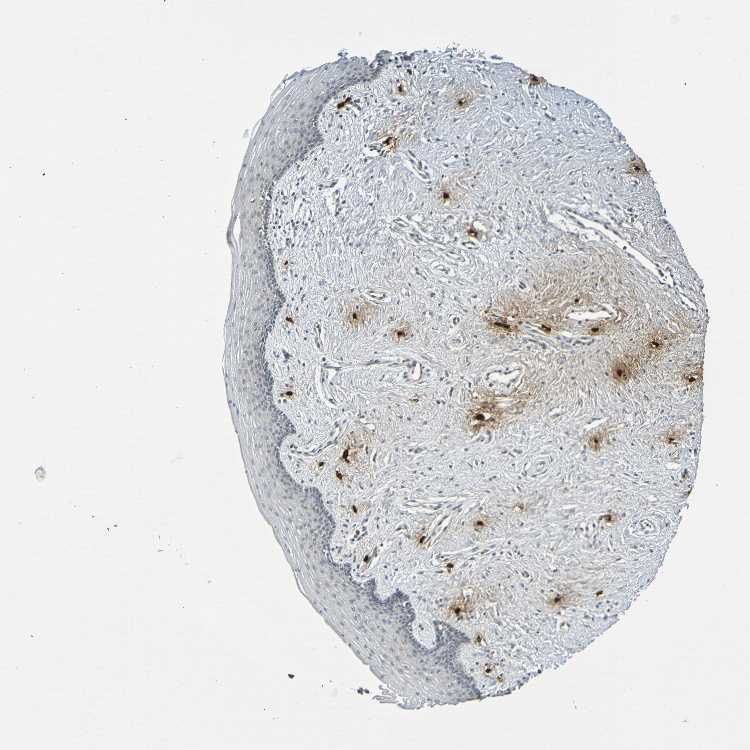

VAGINA - Antibody stainingi

Antibody staining in the annotated cell types in the current human tissue is reported as not detected, low, medium, or high, based on conventional immunohistochemistry profiling in selected tissues. This score is based on the combination of the staining intensity and fraction of stained cells.

Each image is clickable and will lead to virtual microscopy that enables deeper exploration of all samples and also displays staining intensity scores, fraction scores and subcellular localization as well as patient and tissue information for each sample.

Antibody CAB009405

Squamous epithelial cells Not detected